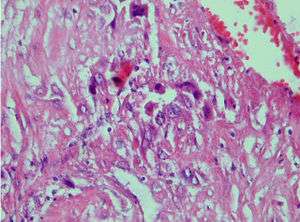

| Photomicrograph showing proliferating intermediate trophoblast with scarce cytotophoblastic and systrophoblastic elements | |